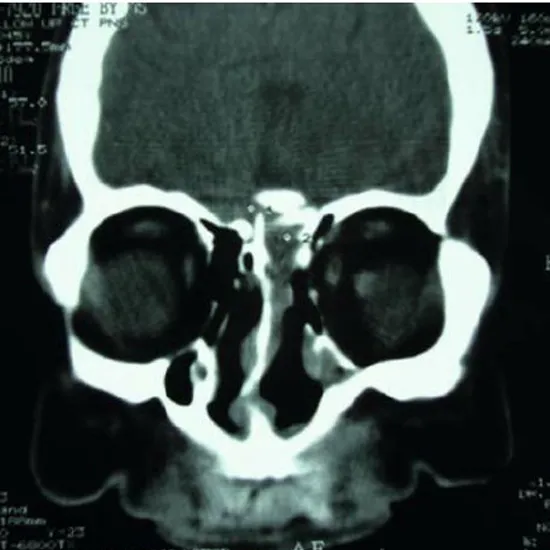

NCCT PNS Sagittal is a Non-contrast computed tomography Para-nasal scan Sagittal view. It is an imaging scan that is used to evaluate the paranasal sinus cavities (The hollow air-filled space within the bones of the face surrounding the nasal cavity). This scan is performed to confirm the presence of a tumor, its size and its location.

• To diagnose the sinusitis

• To diagnose the tumors of the nasal cavity and the size of tumor.

• To detect the sinus infections

• To identify the presence of fluid in sinus cavities.

• To diagnose the existence of abnormal growth or tumors.